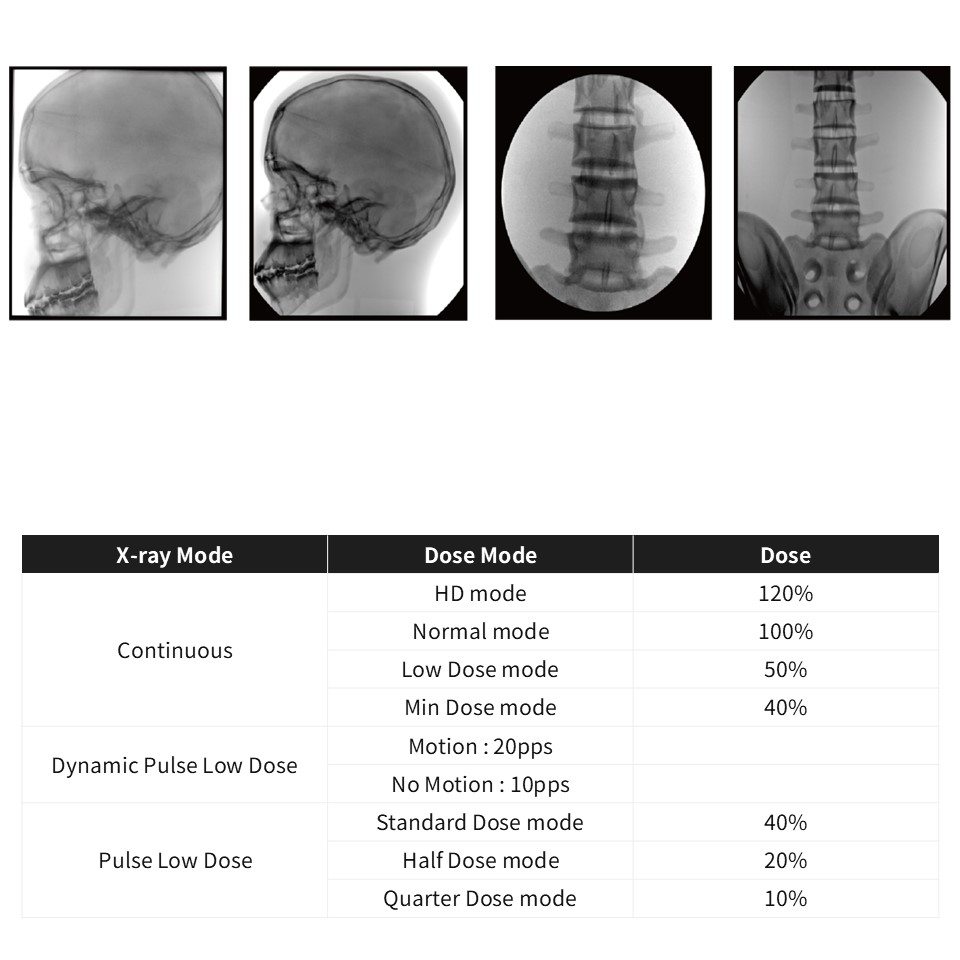

수원, 바른정형외과의원(E3E)

설치사례